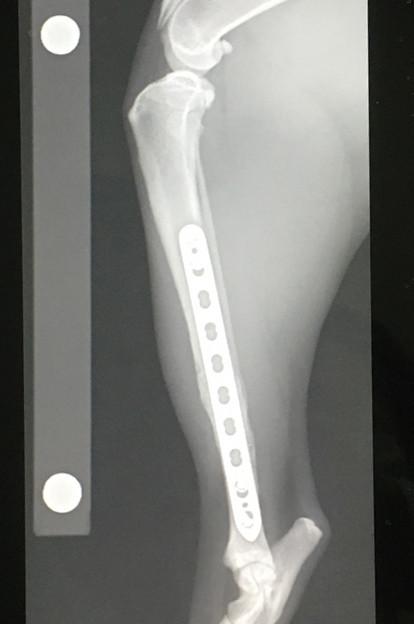

2021年6月、骨折してから約10ヶ月&プレート抜去手術(1回目)から3ヶ月経過しての検診に行ってきました。

レントゲン撮って「順調です」って言われてお会計してくるルーチン。

もう飼い主も先生も今さら特にコメントもなくw。

予定通り次回残りのプレート抜去のスケジュールを決めてきました。

7月中旬ー。